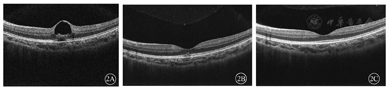

患者男,12岁。因被激光笔照射左眼后眼前固定黑影伴视力下降1 d就诊。眼部检查:视力右眼1.0,左眼0.15(矫正视力不提高)。双眼角膜透明,前房(-),瞳孔等大等圆,晶状体透明,玻璃体未见明显浑浊,右眼眼底视盘界清,视网膜平伏。左眼眼底视盘界清,黄斑中心凹可见浅灰色斑点,视网膜平伏(图1)。眼压右眼14 mmHg,左眼16 mmHg(1 mmHg=0.133 kPa)。FFA:(图1)左眼视网膜血管灌注正常,早期黄斑区可见一斑点状高荧光,晚期荧光增强,范围扩大。左眼OCT:黄斑中心凹区神经上皮层间可见低反射区,外核层反射中断,椭圆体区反射减弱,神经上皮层浅脱离(图2A)。予口服甲钴胺0.5 mg,3次/d。患者2周后复诊:左眼前黑影缩小,右眼1.0,左眼0.2(矫正视力不提高),左眼OCT:黄斑中心凹处视网膜形态恢复,神经上皮层间低反射区消失,外界膜、肌样体区、椭圆体区、交叉区反射断裂存在,断裂处可见高反射团块(图2B)。患者已停用甲钴胺片治疗。1个月后复查:左眼前黑影消失,右眼1.0,左眼1.0,左眼OCT:黄斑中心凹处视网膜厚度恢复正常,外界膜、肌样体区、椭圆体区结构完整(图2C)。

激光致视网膜损伤主要为激光的热效应和光化学效应,而在辐照时间极短的条件下一般认为发生的是热损伤,超过秒量级的辐照时间以后才可能导致激光的光化学反应的发生[6]。Mason[7]、林冰等[8]报道中激光照射可能破坏了视网膜色素上皮的功能从而会导致神经上皮脱离及浆液性渗出。该患者伤后1 d的OCT表现为外核层反射中断,椭圆体区反射减弱,神经上皮层浅脱离,伤后1个月的OCT表现为视网膜各层结构正常,视力恢复,提示神经上皮脱离及外核层反射中断可能存在可逆性的改变。黄斑激光损伤后尚无统一治疗方式,有报道局部或全身应用糖皮质激素、维生素、肌酐以及止血祛瘀明目片等中成药,但治疗结果不一,有视力恢复至损伤前,也有视力无提高甚至损伤进展加重导致黄斑孔形成等[1,2,4,8,9]。因此对于此类激光损伤,关键是预防。家长及学校需对儿童普及安全教育,激光笔不是玩具,任何人在使用激光设备之前,必须阅读激光使用安全手册,尽量避免此类损伤发生。